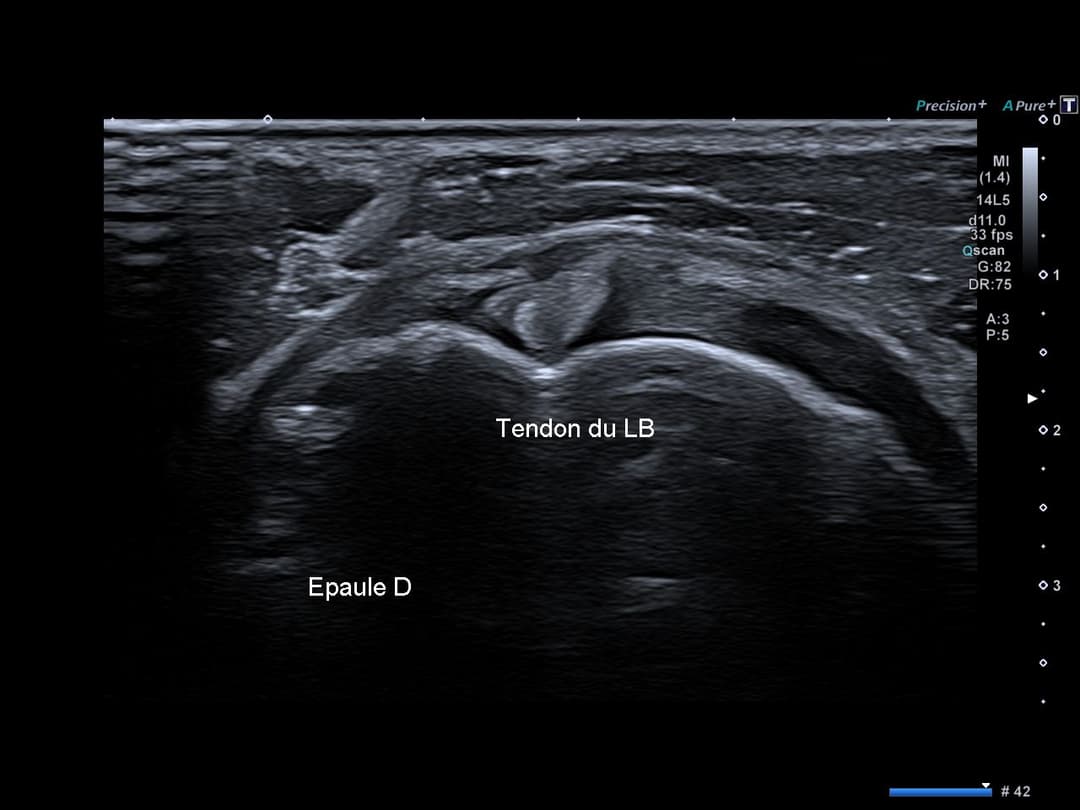

Perte de l'architecture habituelle à double corde du tendon supra épineux, désorganisation hypoéchogène de la face superficielle (bursale) du tendon supra épineux traduisant une rupture partielle.

Comparatif du tendon supra épineux

Rupture de la face bursale du tendon supra épineux avec conservation de sa face articulaire